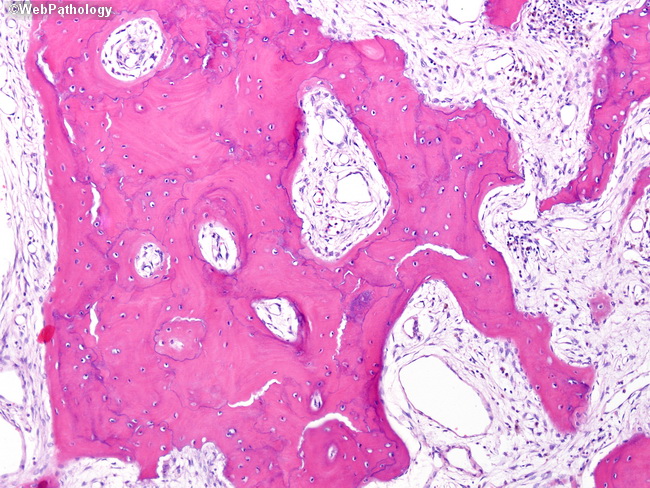

Структура грубоволокнистой костной ткани: наглядные примеры